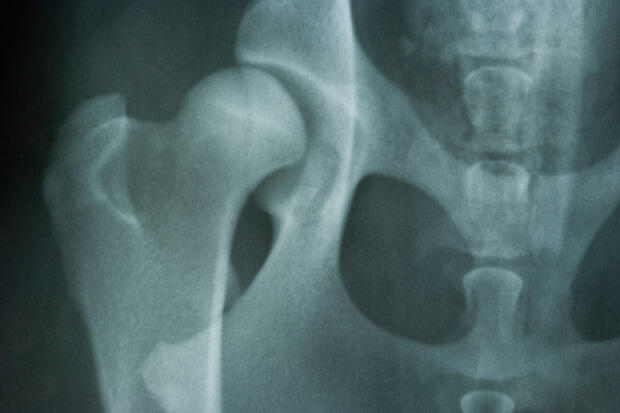

The longer a hip fracture patient stays in a hospital, the more likely that patient will die within 30 days of leaving, according to a study led by Stephen Kates, M.D., chair of the Department of Orthopaedic Surgery at the Virginia Commonwealth University School of Medicine.

There are about 340,000 hip fractures in the U.S. in a year, with the majority of patients between the ages of 81 to 85 years old. The research team from the University of Rochester, where Kates served as a Hansörg Wyss Professor of Orthopaedic Surgery before joining VCU in November, looked at a sampling of more than 188,000 patients admitted to hospitals for hip fracture in the state of New York from 2000 to 2011. Researchers found that hospital stays of 11 to 14 days for hip fracture were associated with a 32 percent increased odds of death 30 days after discharge, compared with stays lasting one to five days. The odds of death increased to 103 percent for stays longer than 14 days.